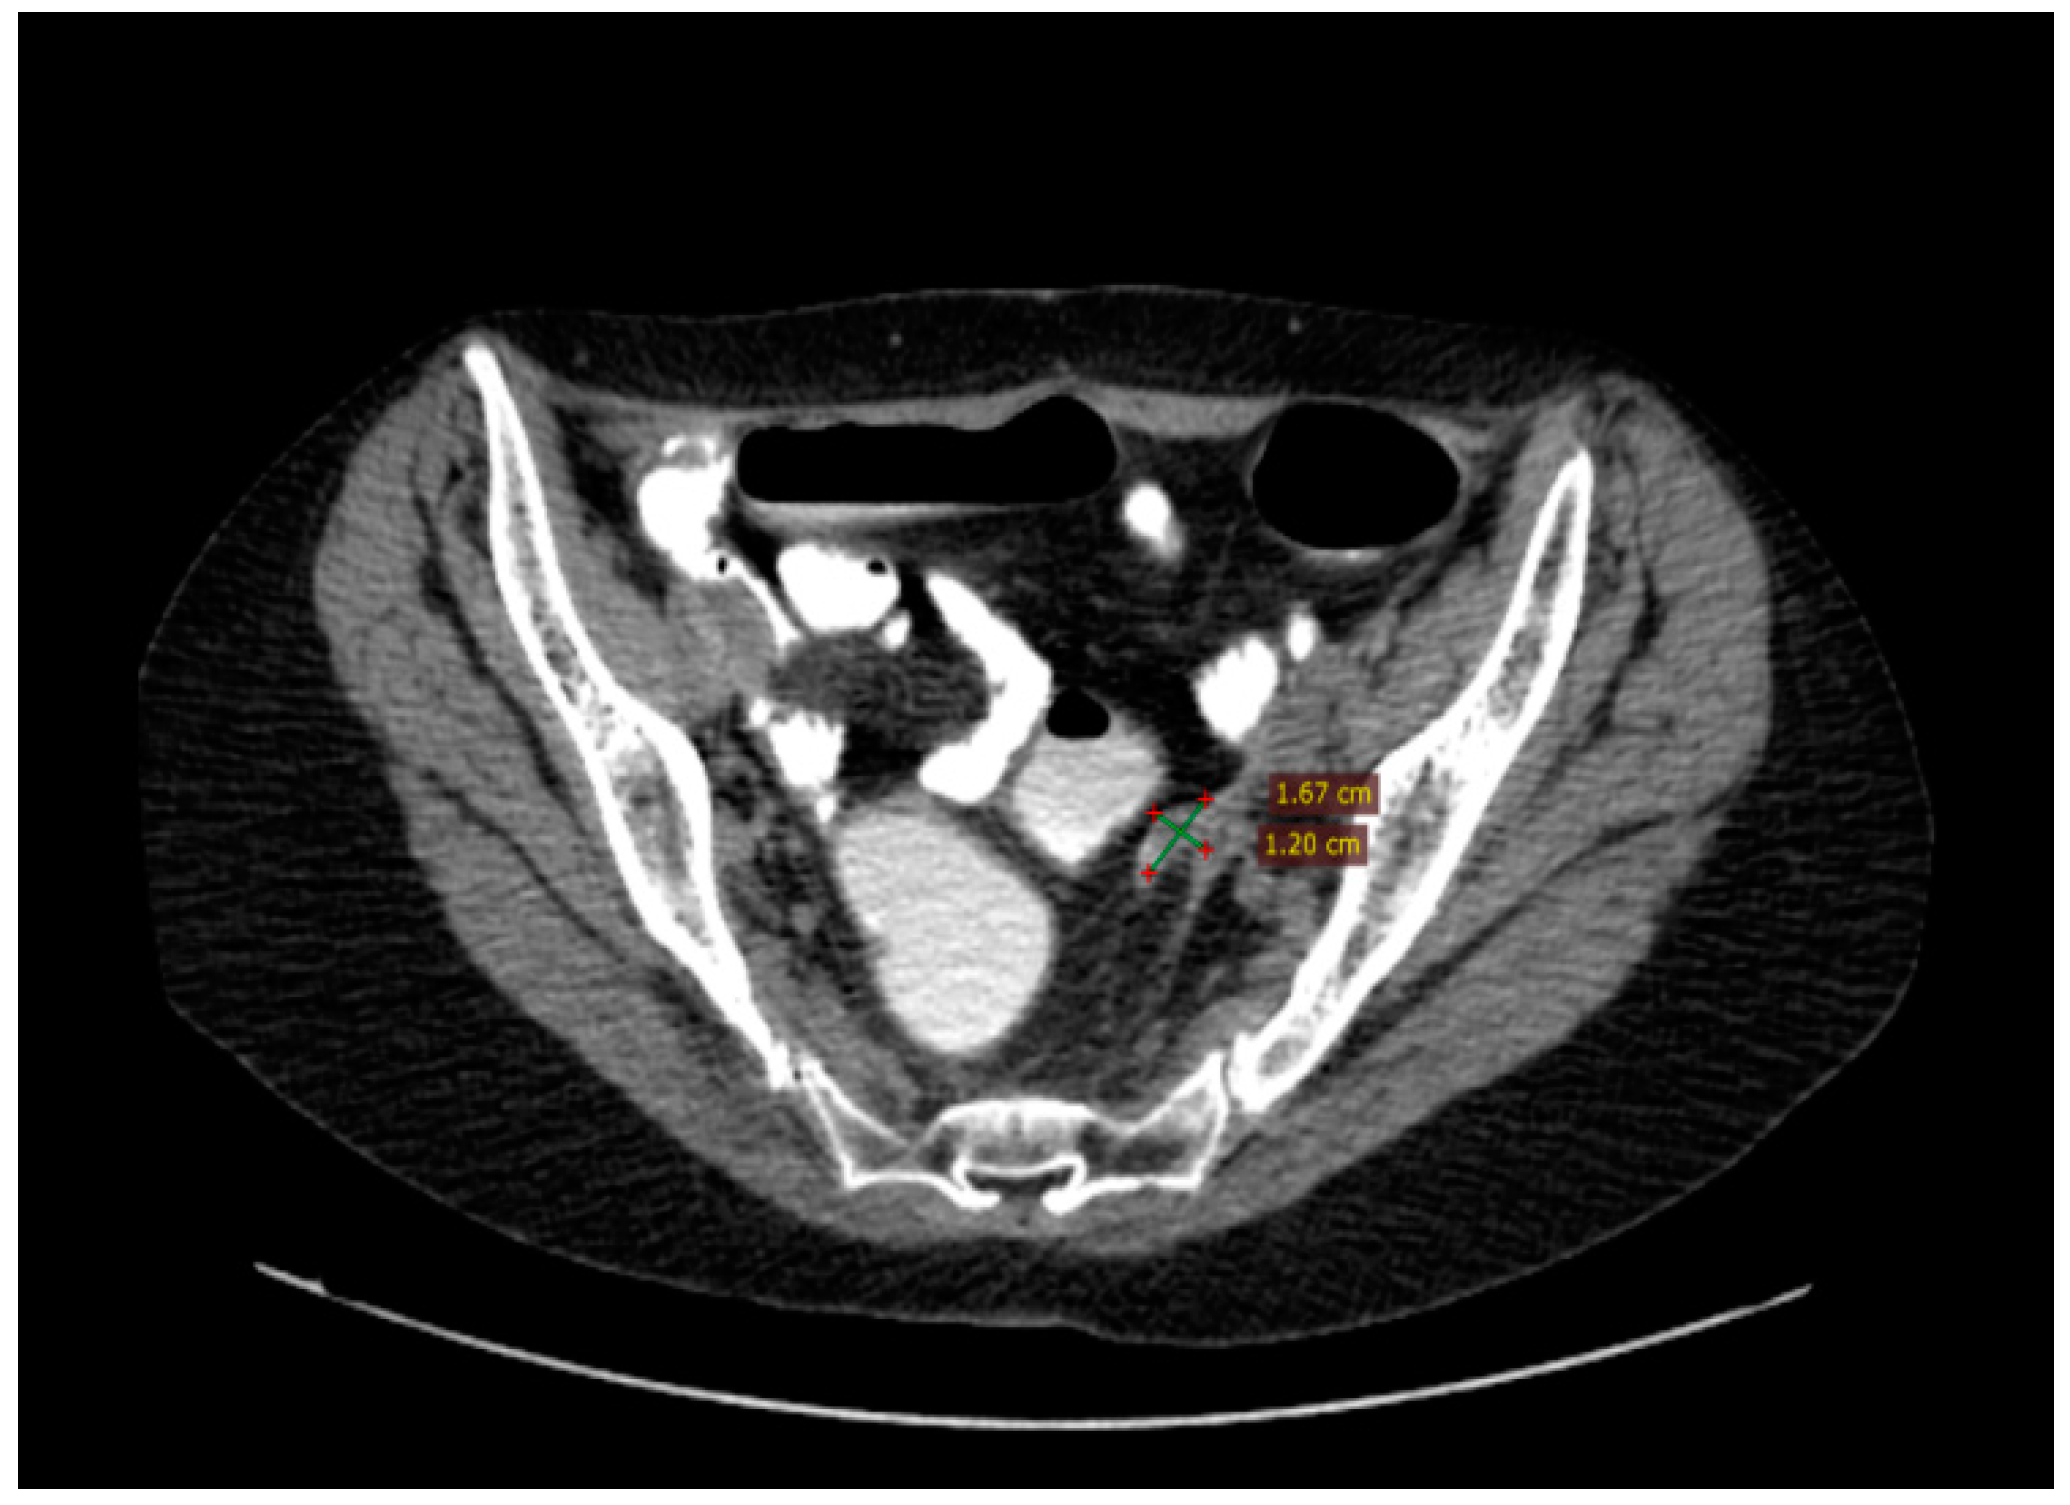

This report includes a case of a 55-year-old postmenopausal female presenting at the Surgical Oncology department of IOB (Institute of Oncology “Prof. Dr. Alexandru Trestioreanu”, Bucharest, Romania) with abdominal discomfort and vaginal bleeding in August 2015. She was diagnosed through a CT scan with a pelvic–abdominal tumoral mass following a routine gynecological consultation in February 2015, but she has refused further investigations (Figure 6).

Figure 6.

Pelvic CT scan from February 2015, six months before presentation at the oncology department.

CT imaging of the thorax, abdomen, and pelvis was conducted in August 2015 and revealed a left ovarian tumor measuring 150/135/120 mm with multiple septations, cystic regions, and solid tumoral tissue, a normal-sized uterus displaced rightward and inseparable from the tumor, peritoneal carcinomatosis, a moderate amount of ascites, and a right pleural effusion occupying about one-third of the hemithorax, leading to atelectasis of the adjacent lung tissue due to compression (Figure 7).

Figure 7.

The baseline CT scan of the thorax, abdomen, and pelvis from August 2015 showing the left ovarian tumor, peritoneal carcinomatosis, ascites, and right pleural effusion, leading to atelectasis of the adjacent lung tissue.